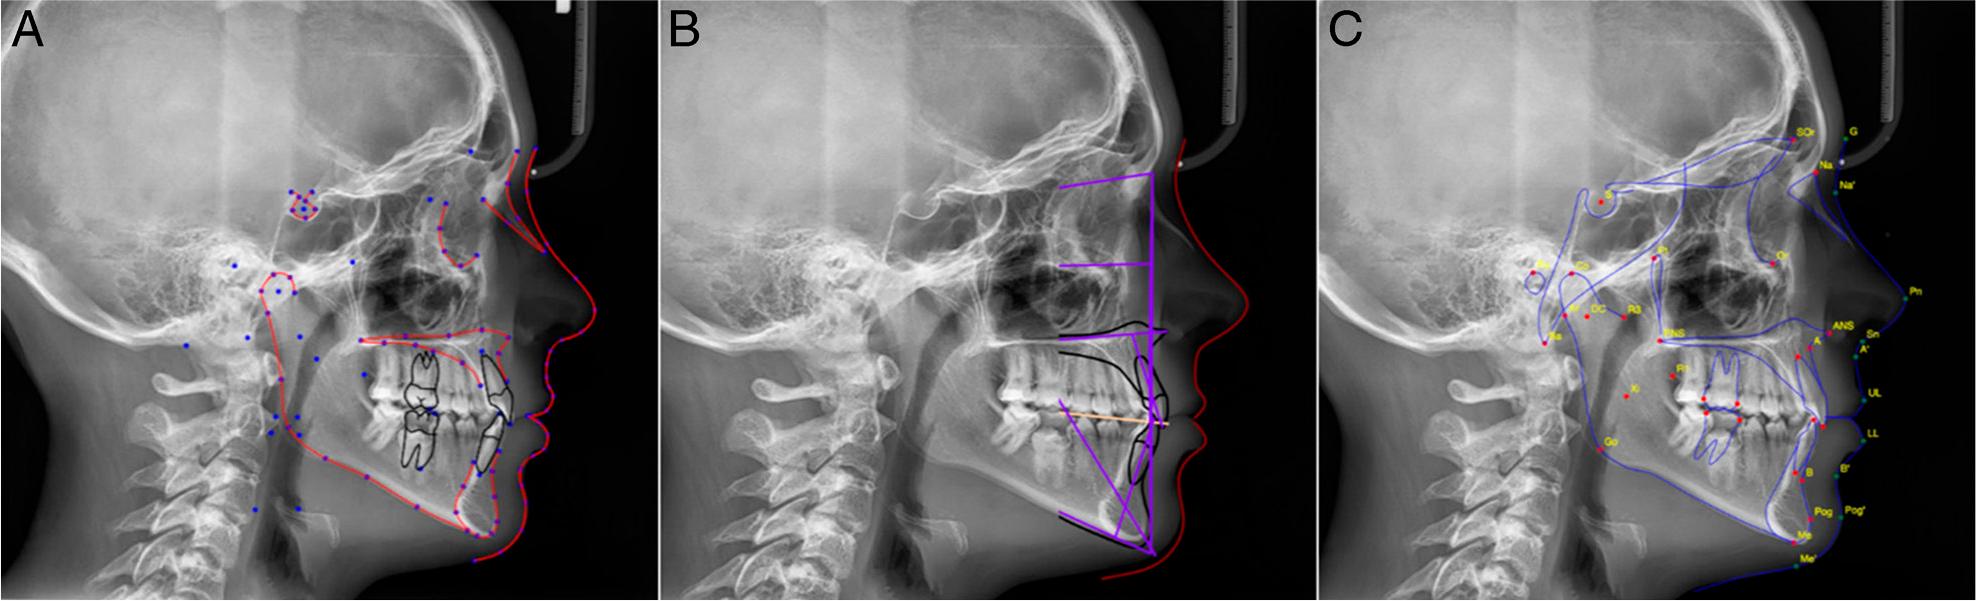

Figure 1.